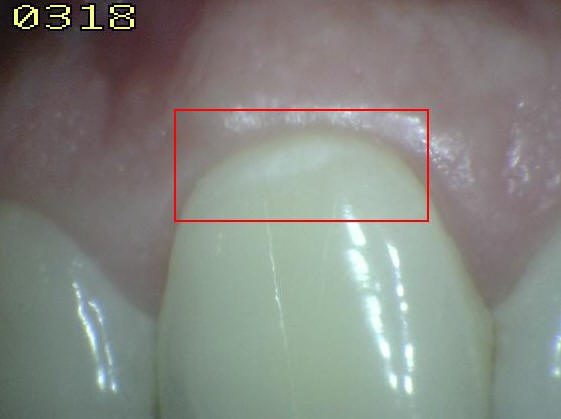

Código 2